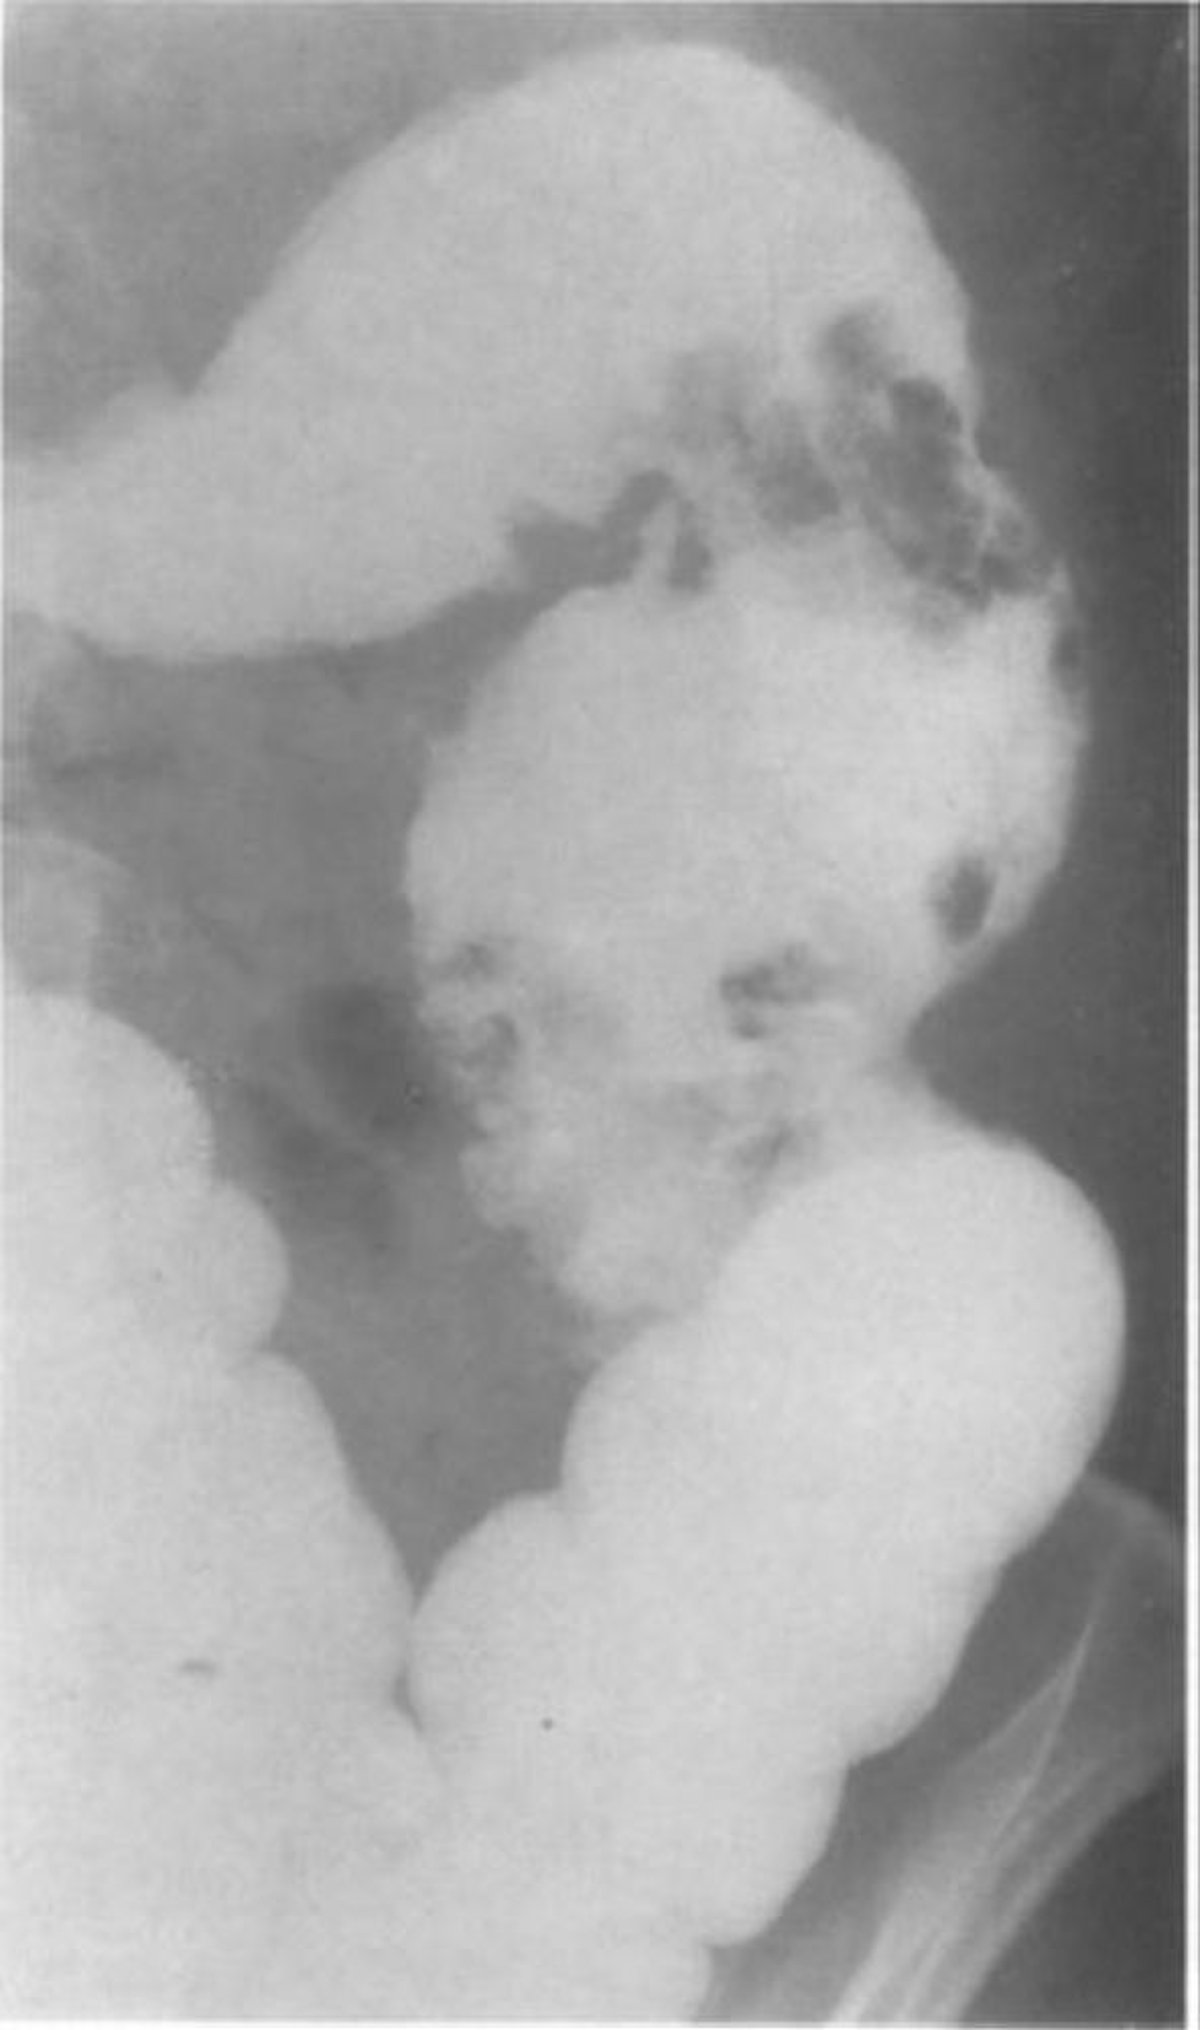

Lavement baryté montrant des pseudopolypes de la muqueuse

Cette image d'un patient atteint de colite granulomateuse montre 2 groupes de gros pseudopolypes dans le côlon descendant.